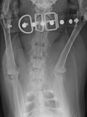

Joey wurde erfolgreich operiert, jetzt macht er fleißig Physio und dann denken wir kein sein Leben beginnen

Joey ist ein junger Cocker Rüde, den wir in seiner Not aufgenommen haben. Da der kleine Genosse öfters mal mit seinen Zähnen versucht seinen Willen durchzusetzen und dazu noch einen alten Schulterbruch hatte, war er einer der Nächsten, der eingeschläfert worden wäre.